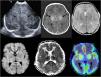

Avances en resonancia magnética (RM)En los últimos años la RM ha experimentado importantes innovaciones, sobre todo en la reducción de los tiempos de exploración. La RM rápida es un método que limita los tiempos de exploración lo suficiente como para evitar la sedación, siendo utilizada habitualmente para el cerebro, pero también en el dolor abdominal agudo y las infecciones musculoesqueléticas. El método Dixon de supresión de grasa es más uniforme y proporciona imágenes con y sin supresión de grasa en una sola adquisición. La imagen por tensor de difusión (diffusion tensor imaging [DTI]) permite cuantificar la difusión anisotrópica en diversas direcciones, con ulterior construcción de mapas de anisotropía representando la dirección de los tractos o tractografía, la cual puede representar cambios microestructurales en el tejido cerebral, tanto los fisiológicos asociados a la mielinización y desarrollo cerebral normal, como en diversos trastornos o en cambios posteriores al tratamiento. Esta técnica ayuda al neurocirujano a reducir la morbilidad al resecar la mayor cantidad de tumor posible, preservando los tractos más importantes de sustancia blanca, como las vías corticoespinales, responsables de la función motora, o el fascículo arqueado, responsable del lenguaje. La perfusión ASL (arterial spin labeling) es un método de perfusión que no requiere gadolinio, pues utiliza el agua de la sangre como marcador endógeno, con la ventaja de su carácter no invasivo. Puede mostrar cambios en la perfusión cerebral en diversas anomalías como ictus, convulsiones, migrañas complicadas, o neoplasias cerebrales (figura 2). La RM espectroscopia (RMs) proporciona información metabólica complementaria a las imágenes neuroanatómicas y es especialmente útil en las neoplasias cerebrales, contribuyendo a determinar el grado de malignidad, así como a valorar la respuesta al tratamiento. La RM funcional (RMf) utiliza los cambios dependientes del nivel de oxigenación sanguínea, siendo su principal utilidad la planificación prequirúrgica previa a la resección de lesiones como tumores cerebrales, malformaciones vasculares o focos epileptógenos cercanos a la corteza elocuente. Las áreas elocuentes del cerebro que se estudian con mayor frecuencia incluyen las áreas motoras, del lenguaje y visuales, mediante diversos paradigmas basados en tareas. La técnica SWI (susceptibility weighted image) es una técnica de eco de gradiente 3D, de alta resolución espacial, que acentúa las propiedades magnéticas de productos sanguíneos, calcificaciones y hierro, siendo sensible en la detección de microhemorragias y en diferenciarlas de las calcificaciones, o en demostrar la vascularización anómala en los tumores de alto grado3.

A)Ecografía transfontanelar realizada en el primer día de vida en neonato a término con hipoxia-isquemia grave que demuestra lesión bilateral de sustancia gris central (flechas). B)RM craneal realizada a los 4días de edad que demuestra lesión bilateral de sustancia gris central en las secuencias T1, T2, con restricción en difusión, con evidencia de perfusión elevada en ASL (flechas), lo cual se ha correlacionado con mal pronóstico.